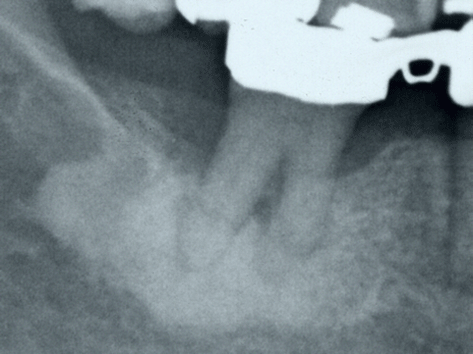

X線写真で根尖部に白い影が見られたとき、その処置をどうしたら良いのか判断に困ることがあります。 患者は62歳、女性で初診時に、下顎左側第一大臼歯の疼痛を主訴に来院しました。腫脹、圧痛等は認められませんでした。そこで口内法X線撮影を行いました(写真1)。根尖部に境界明瞭なX線不透過像を認め、その根尖部の画像診断について、研修医と放射線科医とのQ&A方式でまとめてみました。 放射線科医:どうしましたか? 研修医:分からない症例があるのですが。 放射線科医:どのような症例ですか? 研修医:左下第一大臼歯の根尖部に白い部分があります。 放射線科医:根尖部との関係は?また形態や周囲との関係はどのようになっていますか? 研修医:歯根膜腔の連続性は認めます。また、形態は不 定形で、白い部分の周囲に透過帯を認めます。 放射線科医:白い部分ではなく、不透過像と表現しましょう。 研修医:分かりました。 放射線科医:最終的な所見としては、左下第一大臼歯部の近心遠心根の歯根膜腔の連続性が見られ、その周囲に不定形の不透過像を認め、さらに不透過像の周囲に透過帯を認めるが、その他の部位には何か異常はありますか? 研修医:口内法X線写真では、これ以上の範囲の観察は無理です。 放射線科医:もう少し広い範囲から観察するためにパノラマX線写真を撮りましょう(写真2)。 研修医:はい。分かりました。 放射線科医:パノラマX線写真の所見をいってください。 研修医: 右下臼歯部、左下臼歯部に、境界明瞭で不定形で不均一な不透過像を認めます。 放射線科医:さらに、右上臼歯部にも境界明瞭で不定形で不均一な不透過像を認めますよ。 研修医:気付きませんでした。 放射線科医:診断は全体的に観察してから、局所的に観察しましょう。拡大するのもいいですよ(写真3,4)。 研修医:大学では両側性の疾患は珍しいと習いましたが どうですか? 放射線科医:両側性の疾患は珍しいです。また、上顎にも同様な不透過像を認める症例は非常に珍しいです。 研修医:根尖部の不透過像は初めてみましたが、よくありますか? 放射線科医:通常根尖部の病変と言えば透過像が主で、不透過像は珍しいです。家族歴には、何か問題はありましたか? 研修医:家族歴の問診までは行っていません。 放射線科医:そうですか。家族歴の問診は行ったほうがよかったですね。 研修医:分かりました。でも、画像診断名は何を挙げますか? 放射線科医:骨由来の疾患ではなく、セメント質由来の疾患を考えるべきです。 研修医:どうしてですか? 放射線科医:不透過像と歯根との間に歯根膜腔を認めるからです。ただし、骨とセメント質との区別は困難です。 研修医:分かりました。処置はどうしたらいいですか? 放射線科医:急性症状がないならば経過観察がいいと思いますよ。 研修医:分かりました。 放射線科医:基本的に診断名も大事ですが、その前の段階のX線写真でどの部位に着目するかが大切です。  |

| (写真1:口内法X線写真) | ![]()  |